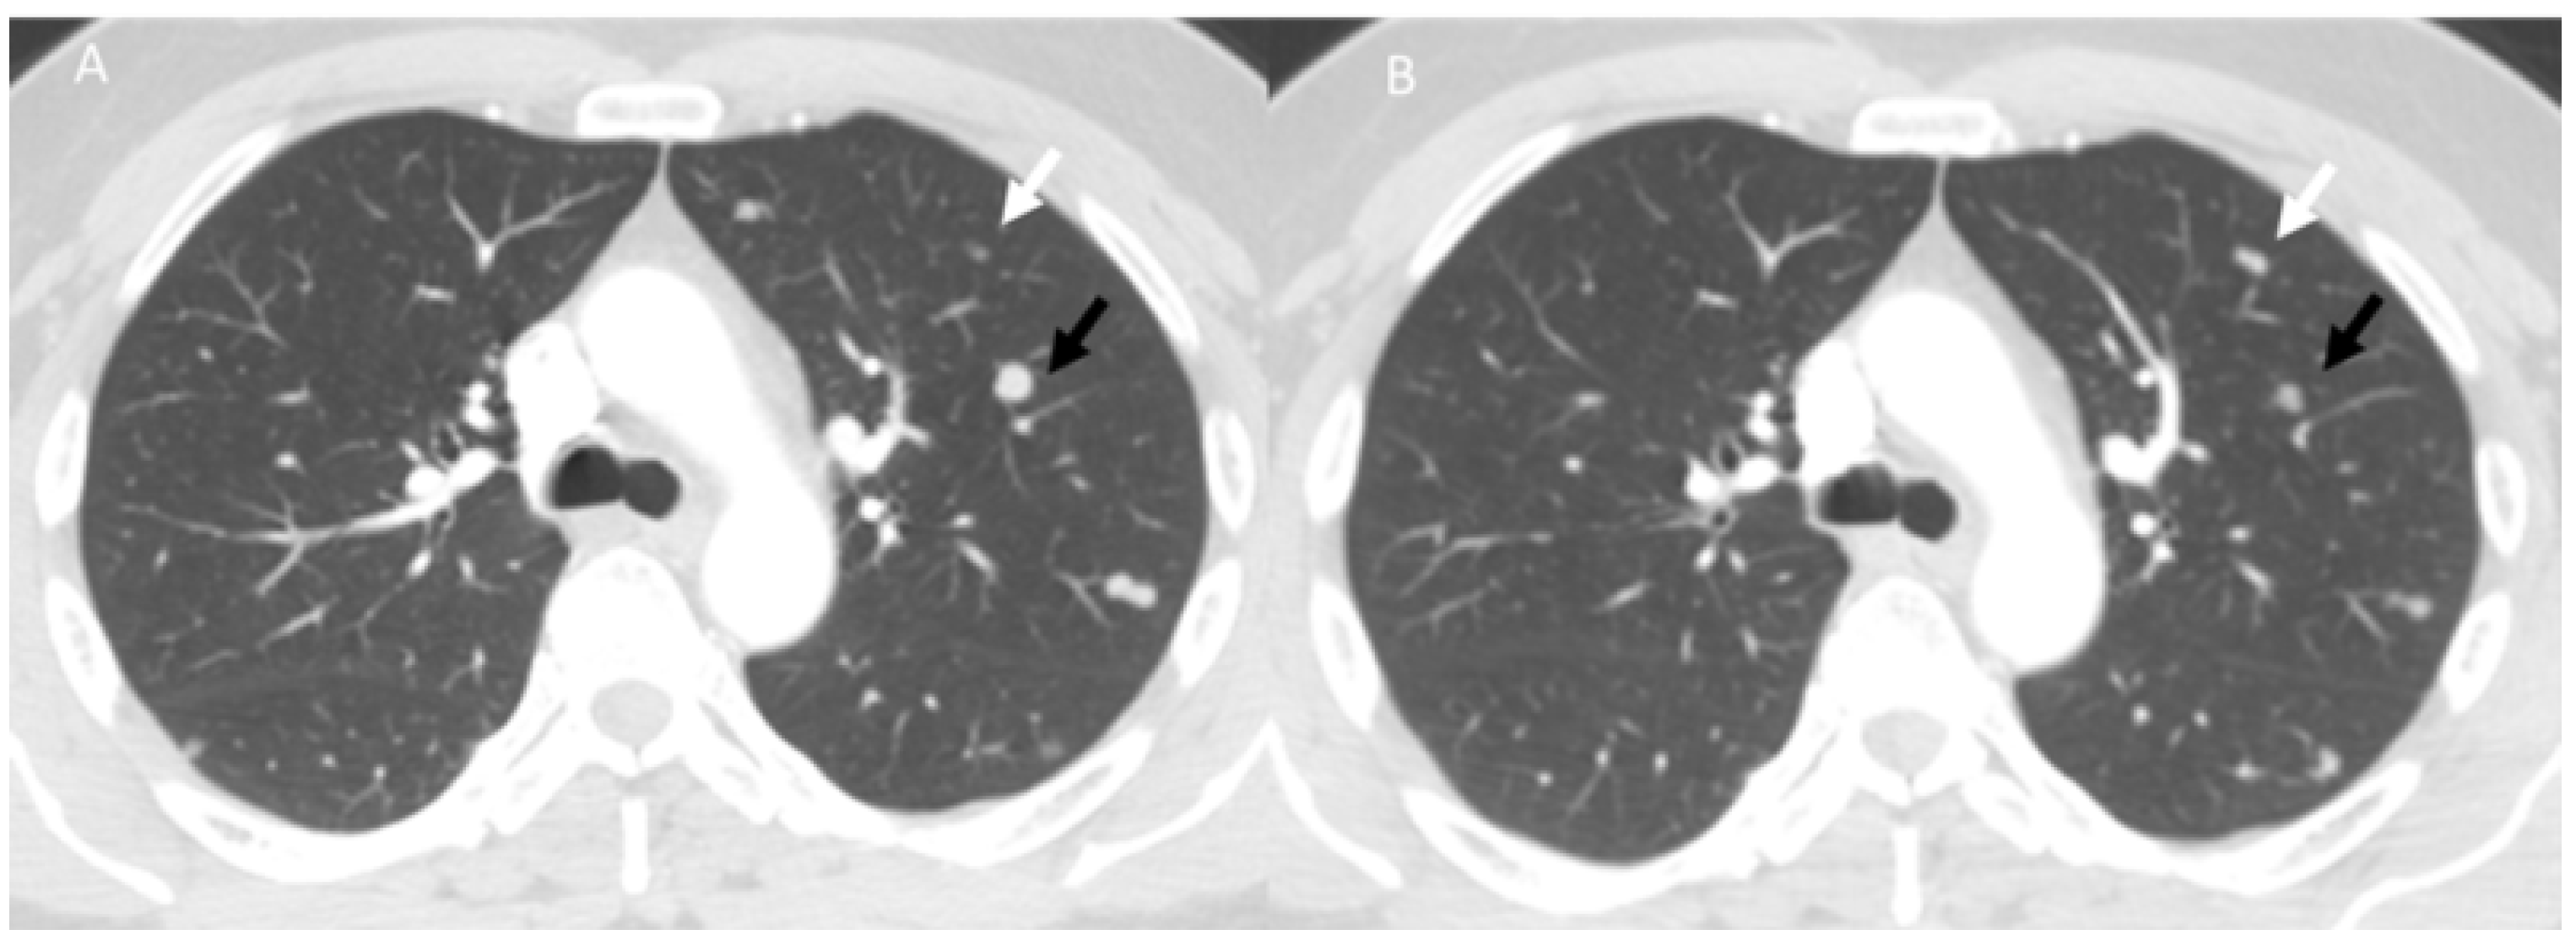

- Khunger, M.; Rakshit, S.; Pasupuleti, V.; Hernandez, A.V.; Mazzone, P.; Stevenson, J.; Pennell, N.A.; Velcheti, V. Incidence of Pneumonitis with Use of Programmed Death 1 and Programmed Death-Ligand 1 Inhibitors in Non-Small Cell Lung Cancer: A Systematic Review and Meta-Analysis of Trials. Chest 2017, 152, 271–281. [Google Scholar] [CrossRef] [PubMed]

- Kalisz, K.R.; Ramaiya, N.H.; Laukamp, K.R.; Gupta, A. Immune Checkpoint Inhibitor Therapy-related Pneumonitis: Patterns and Management. Radiographics 2019, 39, 1923–1937. [Google Scholar] [CrossRef] [PubMed]

- Delaunay, M.; Cadranel, J.; Lusque, A.; Meyer, N.; Gounant, V.; Moro-Sibilot, D.; Michot, J.M.; Raimbourg, J.; Girard, N.; Guisier, F.; et al. Immune-checkpoint inhibitors associated with interstitial lung disease in cancer patients. Eur. Respir. J. 2017, 50, 1700050. [Google Scholar] [CrossRef]

- Suresh, K.; Voong, K.R.; Shankar, B.; Forde, P.M.; Ettinger, D.S.; Marrone, K.A.; Kelly, R.J.; Hann, C.L.; Levy, B.; Feliciano, J.L.; et al. Pneumonitis in Non–Small Cell Lung Cancer Patients Receiving Immune Checkpoint Immunotherapy: Incidence and Risk Factors. J. Thorac. Oncol. 2018, 13, 1930–1939. [Google Scholar] [CrossRef]

- Tay, R.Y.; Califano, R. Checkpoint Inhibitor Pneumonitis Real World Incidence and Risk. J. Thorac. Oncol. 2018, 13, 1812–1814. [Google Scholar] [CrossRef]